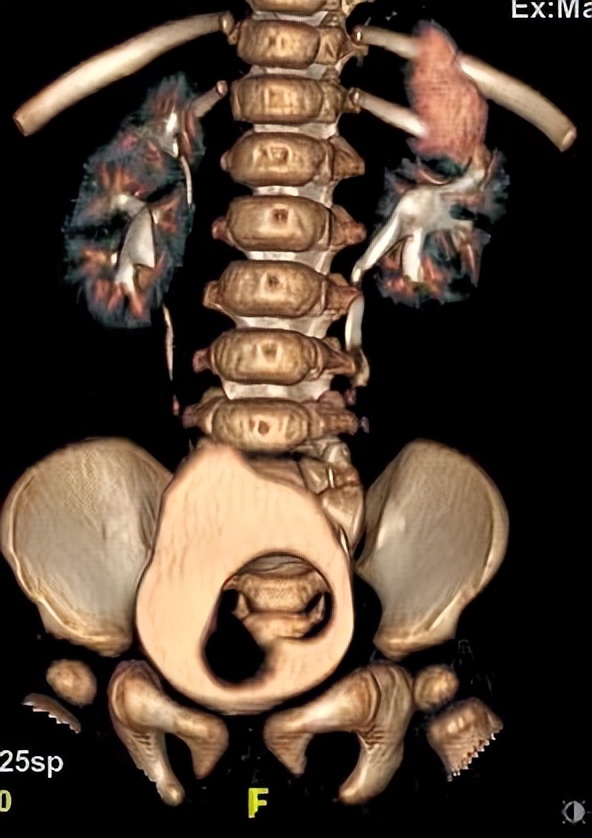

通俗地说,就是一个肾有两套的肾结构,是两套相互独立的肾盂肾盏系统,一个肾重复畸形具有上肾和下肾两个单位,可分别由两根输尿管引流各自集合系统的尿液,称为重复输尿管( 引流上肾或者下肾的输尿管分别被称为“上肾输尿管”和“下肾输尿管”)。在临床上,重复肾还是比较常见的。有研究发现,每1500个小孩中就有1个重复肾小孩。重复肾可以是单侧的,也可以是双侧的,单侧更多见。

根据两根输尿管是否汇在一起,可分为完全性和不完全性( Y 形)两种。不完全性重复尿管可以汇合于输尿管的任何部位,较为常见的是肾盂输尿管连接部相连,或输尿管连接于远端接近膀胱水平。

4、彩超联合CTU检查,可明确绝大部分重复肾和重复输尿管。